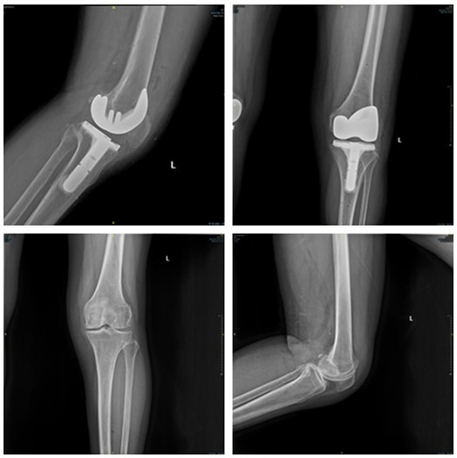

同时,该手术机器人配合独有的内轴型膝关节假体,极大降低了因常规手术技术问题造成关节松动、力线不准、关节脱位等情况的发生率。患者术后X光检查报告显示,机器人辅助截骨能够实现精准力线恢复,患者预后效果良好,证明了该手术机器人相对传统手术具有独特的临床优势。